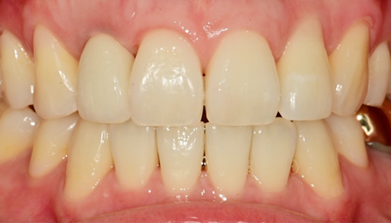

임플란트를 식립하고 동시에 보철물도 완성해드립니다.

내원 당일 이루어지는 임플란트 기술력! 하루 완성 임플란트는 당일에 식립하고

임시 보철물까지 완성됩니다.

일상생활이 가능하도록 임시 보철물 완성